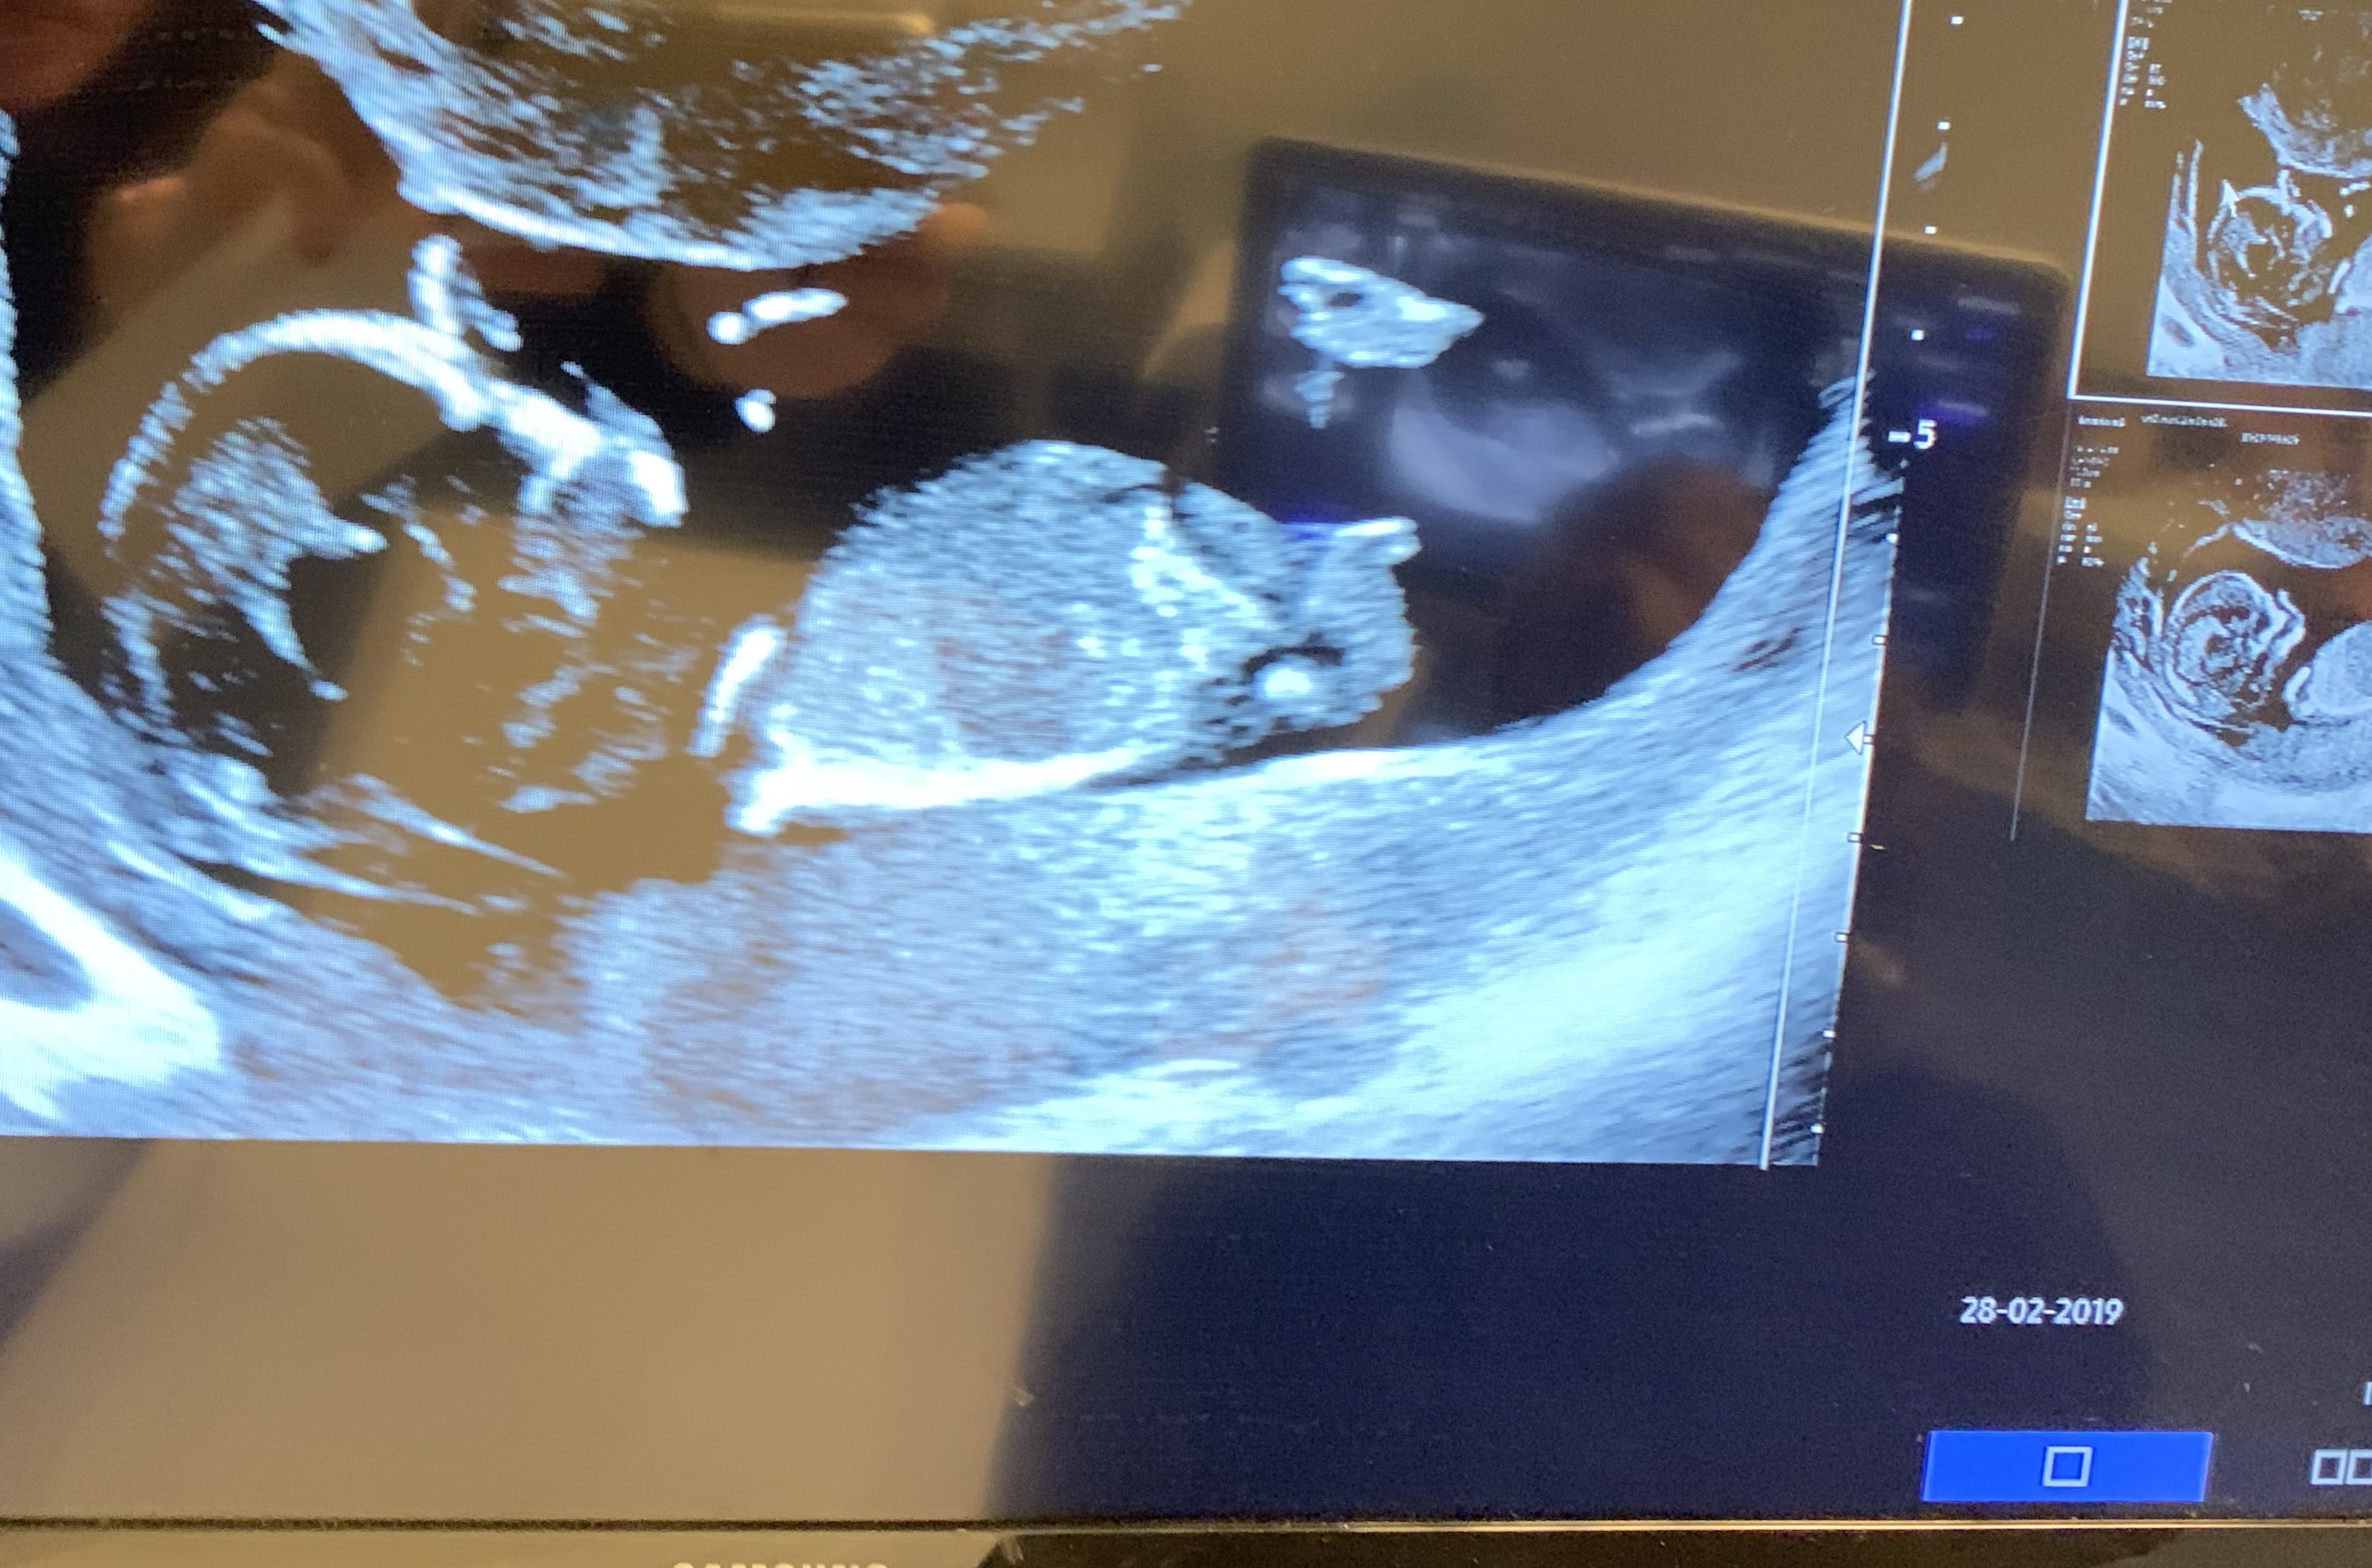

I had an extra Ultrasound because the OB couldn’t find the heartbeat.

I could make photo’s from the screen. Attachment 41233